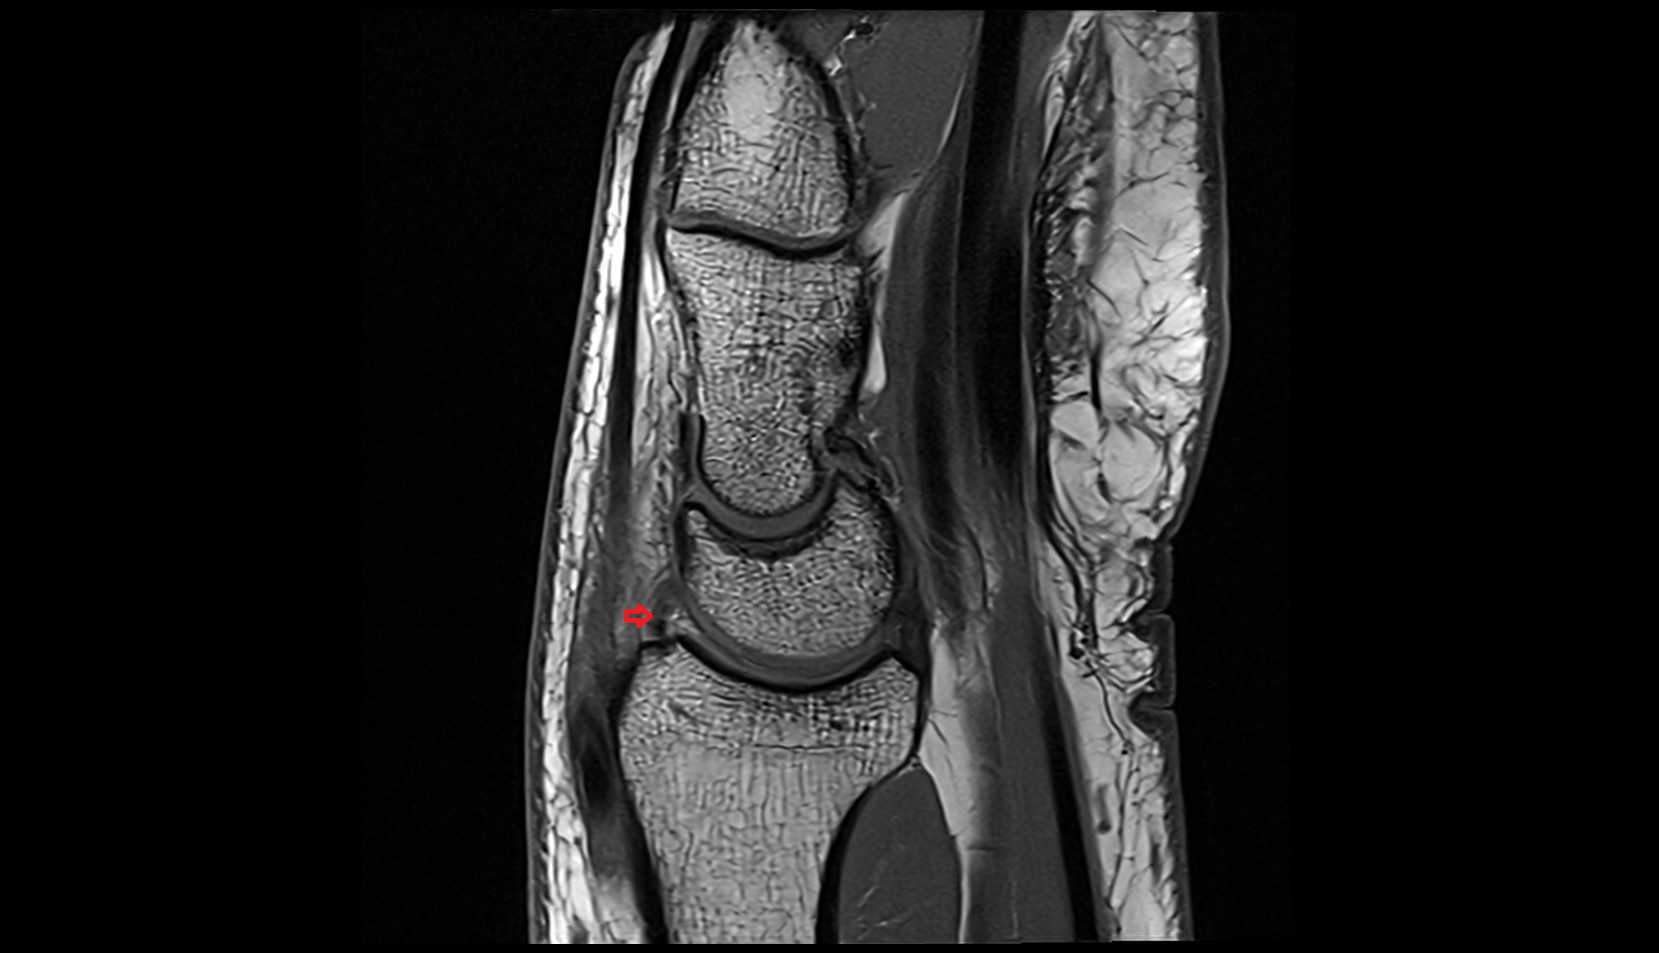

- Knee Joint